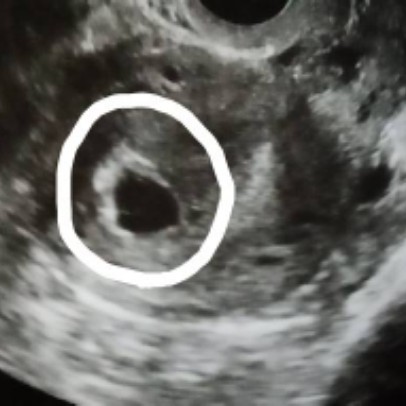

ถุงตั้งครรภ์ 6 สัปดาห์ ซาวไม่เห็นตัวเด็ก เครียดเลยค่ะ

ตั้งครรภ์ 6 สัปดาห์ค่ะ คุณหมอนัดซาวเจอถุงตั้งครรภ์ แต่ยังไม่เห็นตัวเด็ก คุณหมอบอกว่าเห็นถุงไข่แดงข้างใน ตอนนี้แม่เครียดกลัวเปนท้องลม ตอนแม่ๆ6สัปดาห์ ซาวเปนแบบไหนกันบ้างคะ